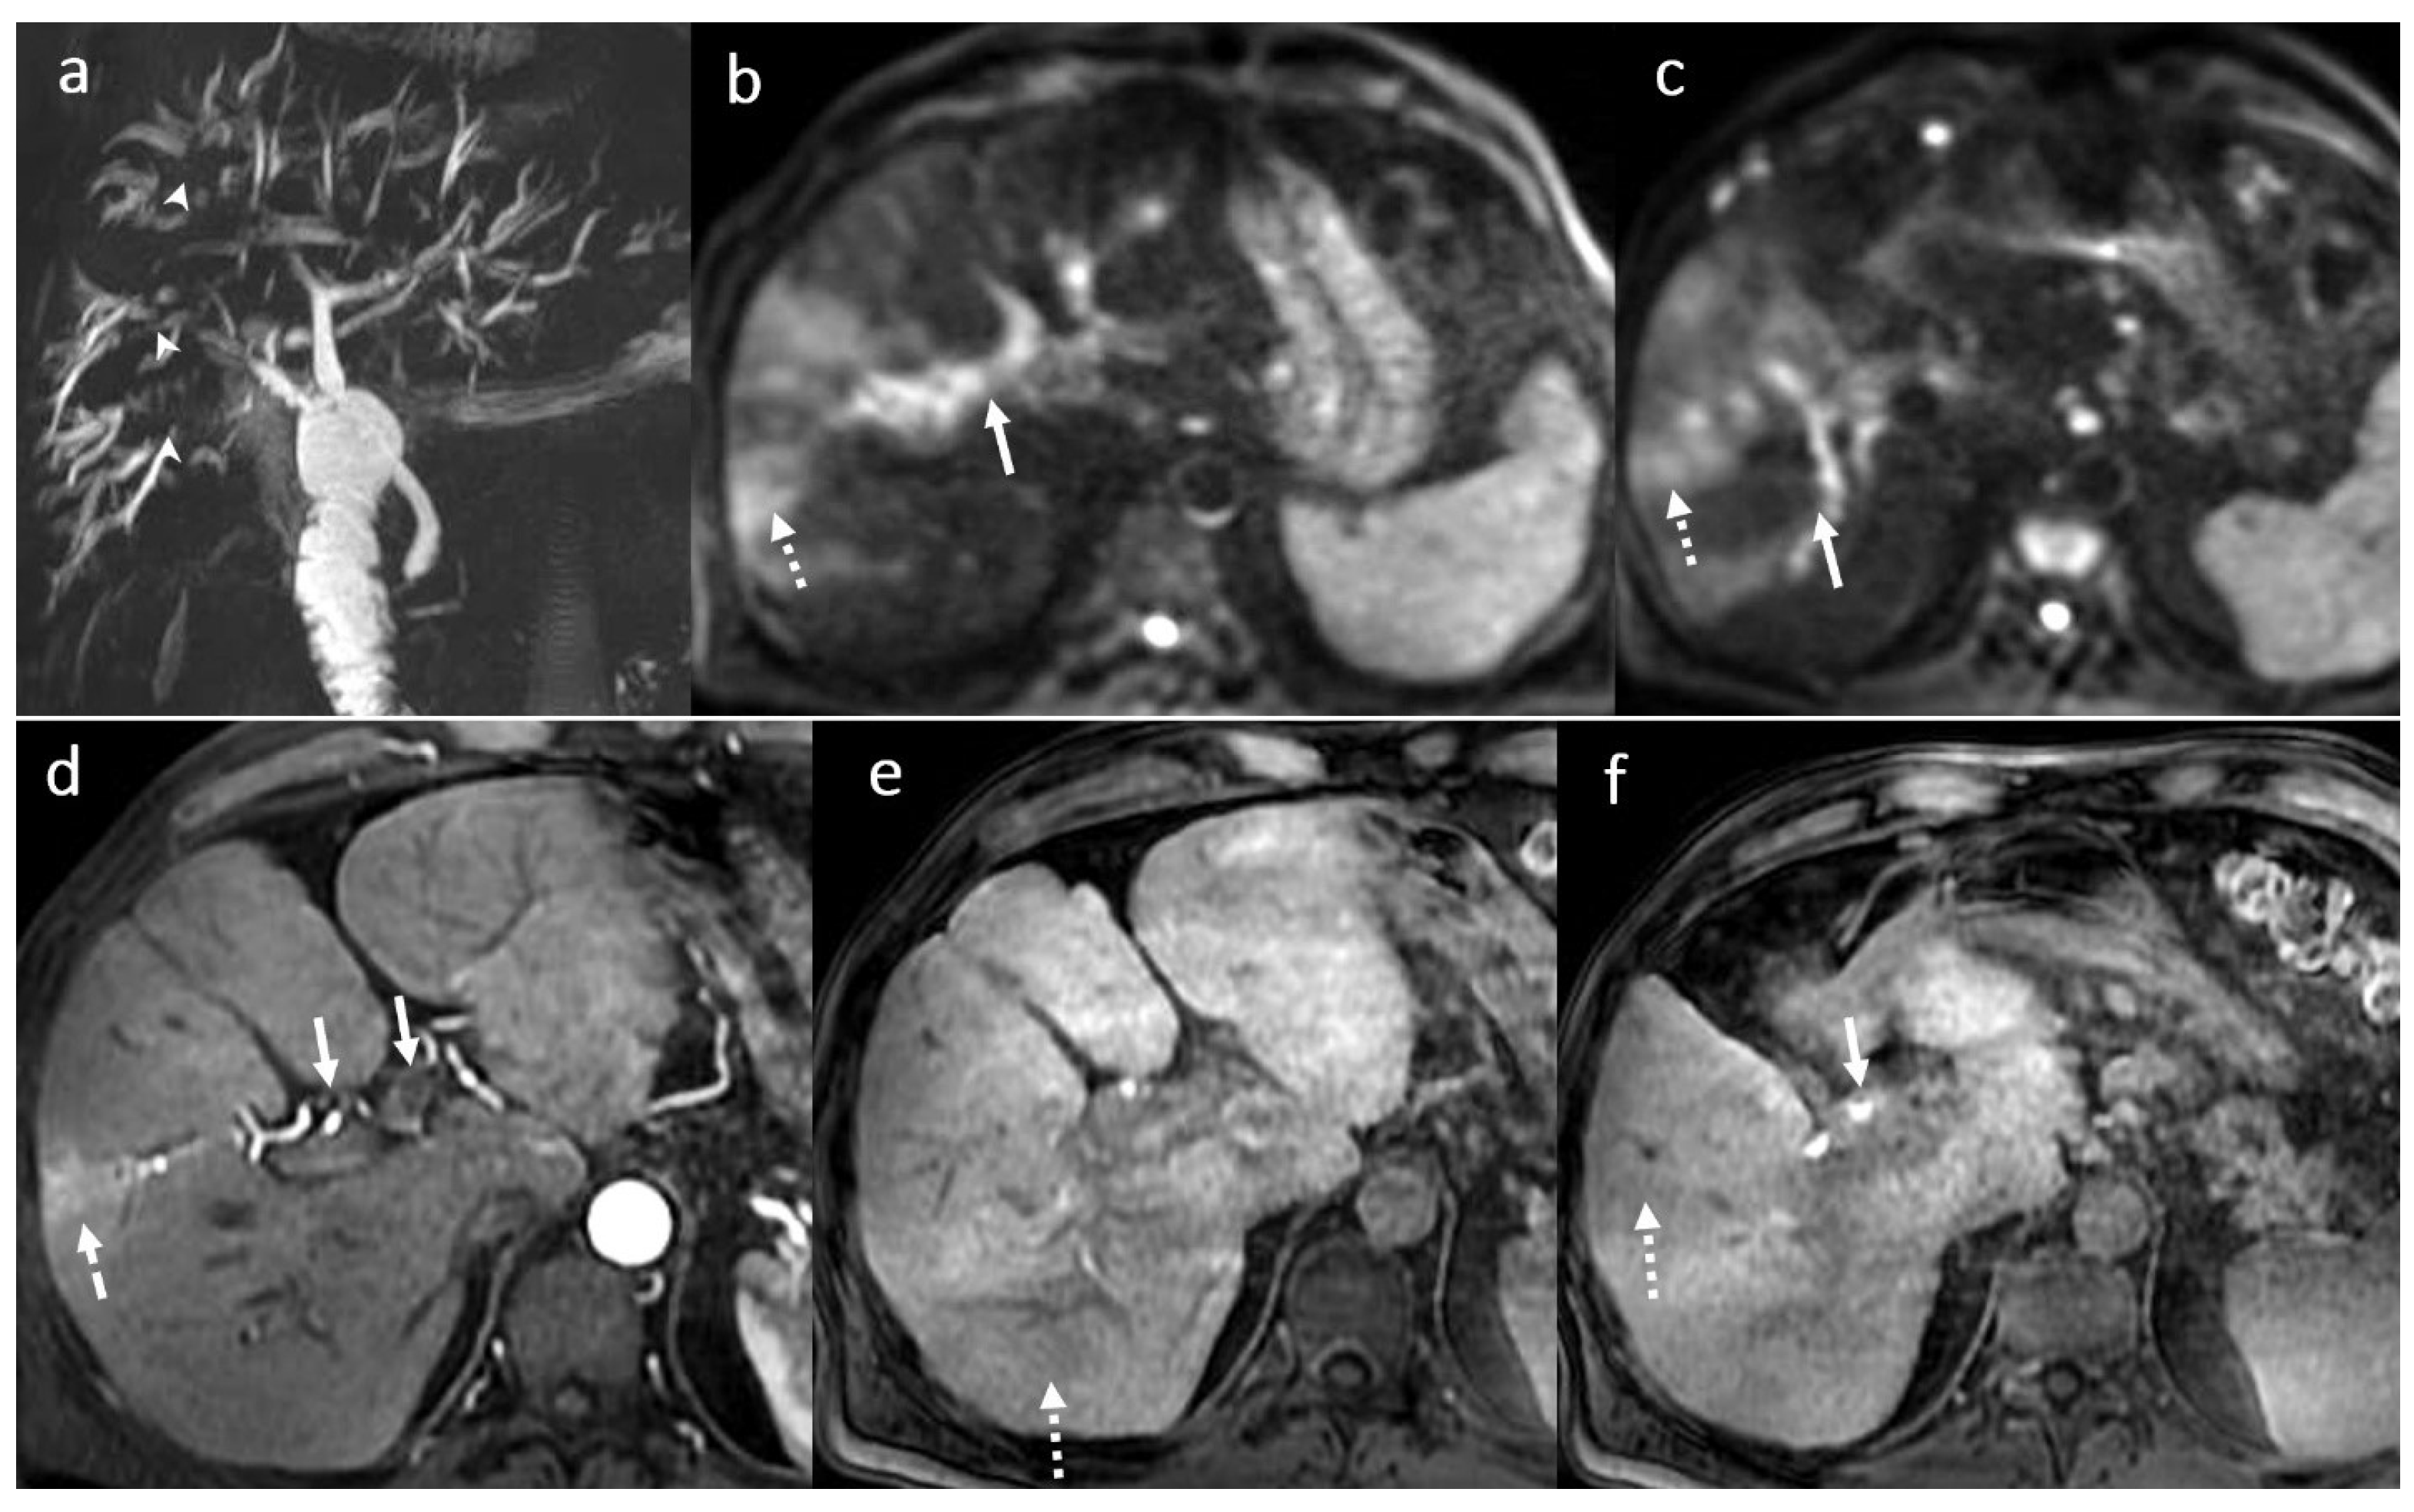

3.8. Primary Sclerosing Cholangitis

3.9. Other Changes